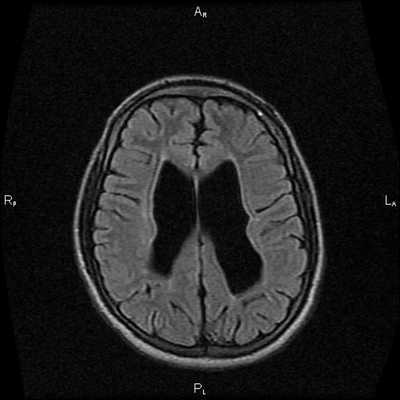

Этот высокотехнологичный метод визуализации анатомических структур, не связанный с воздействием рентгеновского излучения, позволяет безопасно и с высокой эффективностью определить этот диагностический показатель у пациента. МР-диагностика определяет высокое внутричерепное давление по следующим «маркерам»: частично пустое турецкое седло, расширенные оболочки зрительных нервов, уплощенные задние части глазных яблок, щелевидные желудочки.

При МРТ головного мозга установлено: МРТ признаки хронической недостаточности мозгового кровообращения; выраженная открытая внутренняя гидроцефалия, свидетельствующая о признаках атрофических изменений в головном мозге.

![МРТ снимок внутричерепного давления]()